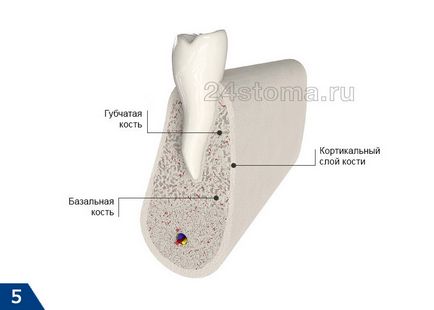

За да се разбере къде да се инсталира на имплантите в различни техники за имплантиране - поглед към анатомията на челюстта костната тъкан на (ris.4-5). Jawbone не е еднакъв в неговата плътност. Корените на естествените зъби са по-меки пореста кост алвеоларна. Порести кост е много пореста, и поради по-ниската му плътност е най-податливи на атрофия - особено в тези места, където са били отстранени зъбите.

Класически импланти са посочени точно в порести костни слоеве, и затова за тези импланти е много важно достатъчно пореста кост на алвеоларния процес. Но инсталирането на базални импланти се случва в по-дълбоките слоеве и плътна кост. Това се нарича базално кост, и то почти не подлежи на атрофия дори и при липса на зъби.

Някои модели на базални импланти могат да имат много широк диаметър на нишките, така че те, на първо място, е добре дефинирана в повечето от базалната костта, и второ - също са bikortikalnuyu фиксация. Това означава, че краищата на нишките ще подпира вътрешната много трудно на костния мозък, която покрива външната страна на челюстта от всички страни.

Важно: това се дължи на факта, че работата на тези импланти в същото време и е с базалната и bikortikalny видове фиксация - осигурява всички основни предимства на импланти базалната тип, например, няма нужда от присаждане на кост, или възможност за незабавно протеза.